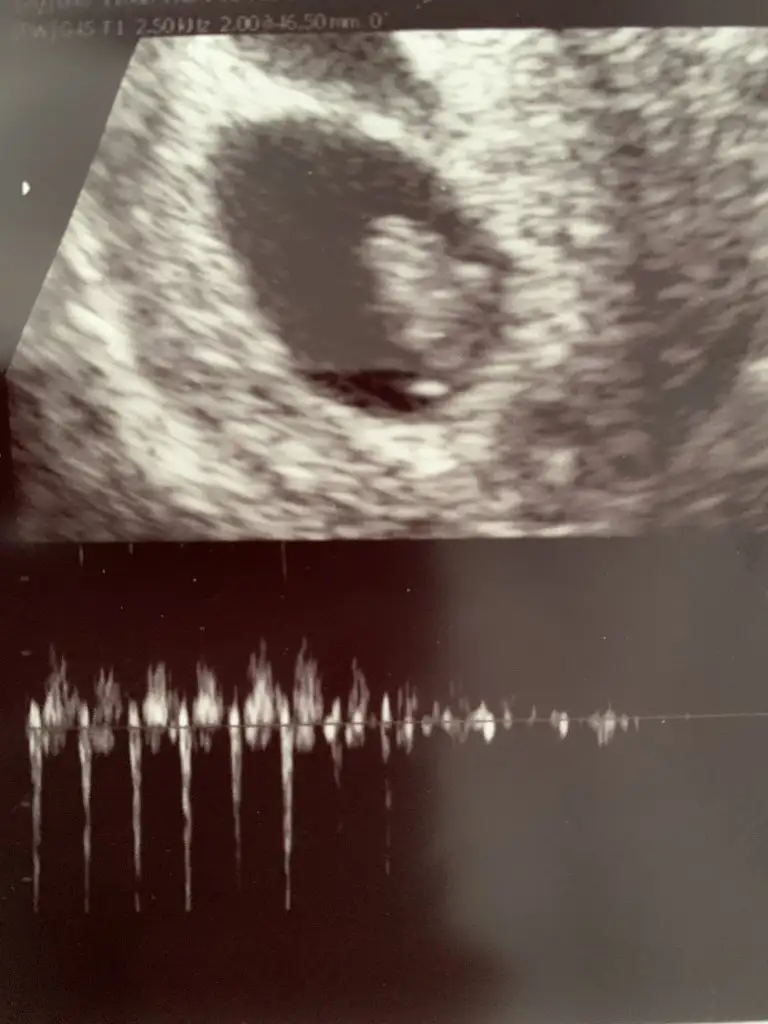

kuzum görüntüyü düz çekip atar mısın, bebek sol alttaki mi? o sanki yolk sac gibiSelam 6+3 teki foto ile ben de geldim

kuzum karından bakılmıştır diye tahmin ediyorum. Tosun paşa gibi duruyor.Merhaba. Ultrason fotoğrafım tam 8 haftalıkken. Bana da tahminde bulunabilir misiniz acaba. Çok teşekkür ederim.